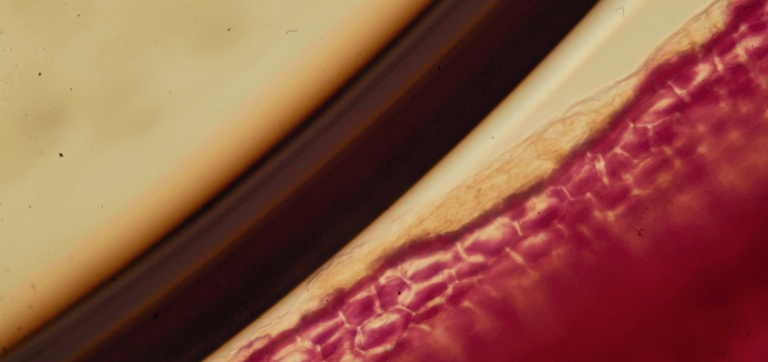

What is Butyrate? A Guide to the Gut’s Superstar Metabolite

7 minutes

Postbiotics: Why These Microbial “Leftovers” Matter for Your Gut

8 minutes

The Need to Feed: How to Increase Butyrate From the Inside Out

6 minutes